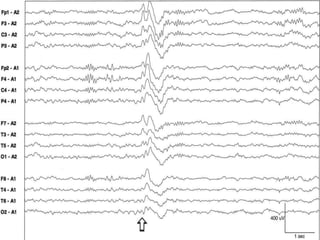

Slow rolling (lateral) eye movements during stage I sleep

Drowsiness (Stage 1)

 Alpha dropout

 Slow eye movement

 Increased beta activity over the frontocentral

regions

 Diffuse rhythmic theta activity with anterior

predominance

 Deep drowsiness is marked by the vertex waves

and POSTS that persist during light sleep and deep

sleep

 Hypnagogic hypersynchrony